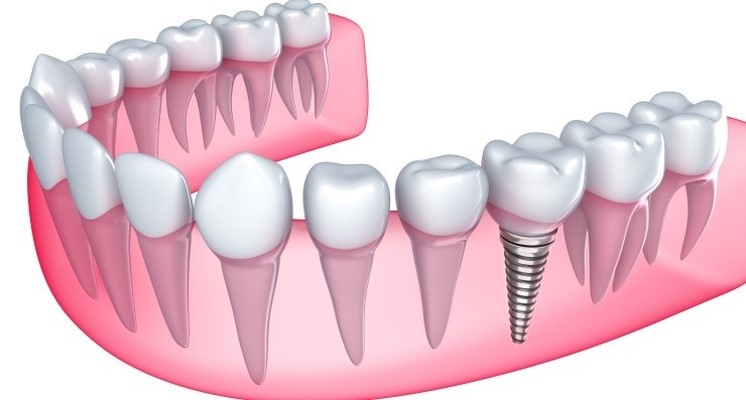

02 임플란트의 강력한 골결합력

음식을 씹을 때 흔들리거나 이물감이 들지 않도록 임플란트가 뼈와 강하게 결합되는 것이 중요한데요. 이는 임플란트의 수명과 직결되는 요소로 친수성이 높은 칼슘 임플란트를 사용하여 임플란트와 치조골간 골 생성이 치밀하고 우수하여 강한 골 결합력을 유지하도록 해야 합니다.